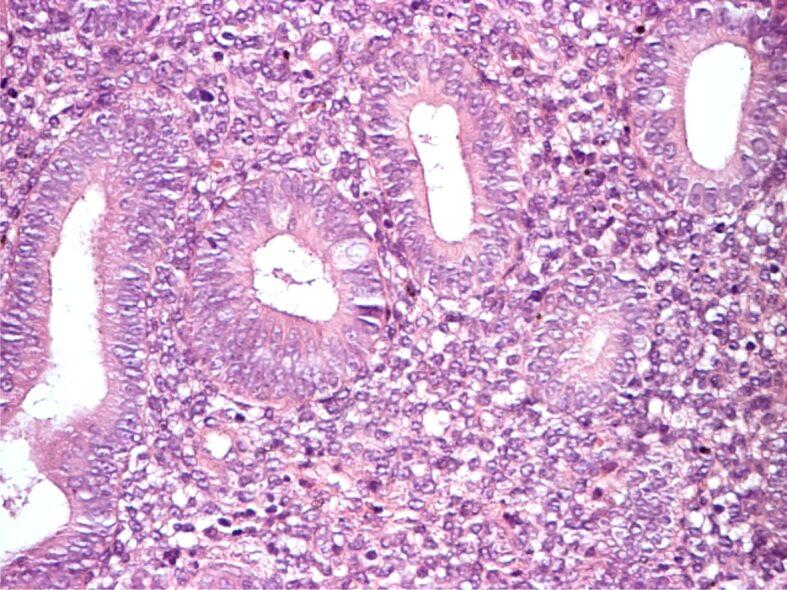

PATIENTS, MATERIALS AND METHODS: The inflammatory response in 20 female patients who underwent minimally invasive gynecological surgery under which intravenous anesthesia was performed. Depending on the combination of anesthetics used, we subdivided the study group into two groups, Group 1 consisting of the patients (n=10) who were given for total intravenous anesthesia, the combination with Midazolam+Fentanyl, and Group 2 (n=10) the patients who received the combination of Propofol+Fentanyl, respectively. Surgical interventional procedures included day surgery: diagnostic and operative hysteroscopy, endometrial ablation, surgical treatment of vulvar disorders. Serological profiling of patients was performed by dosing the serum concentration of nucleotide-binding domain (NOD) and leucine-rich repeat protein 3 (NLRP3) inflammasomes, interleukin (IL)-6, tumor necrosis factor-alpha (TNF-α), IL-10 before and two hours after the surgical procedure.

In our study, we found that in both groups of patients (Midazolam+Fentanyl - Group 1, Propofol+Fentanyl - Group 2), NLRP3 and cytokines concentrations in the serum were higher after MIS than those before MIS.